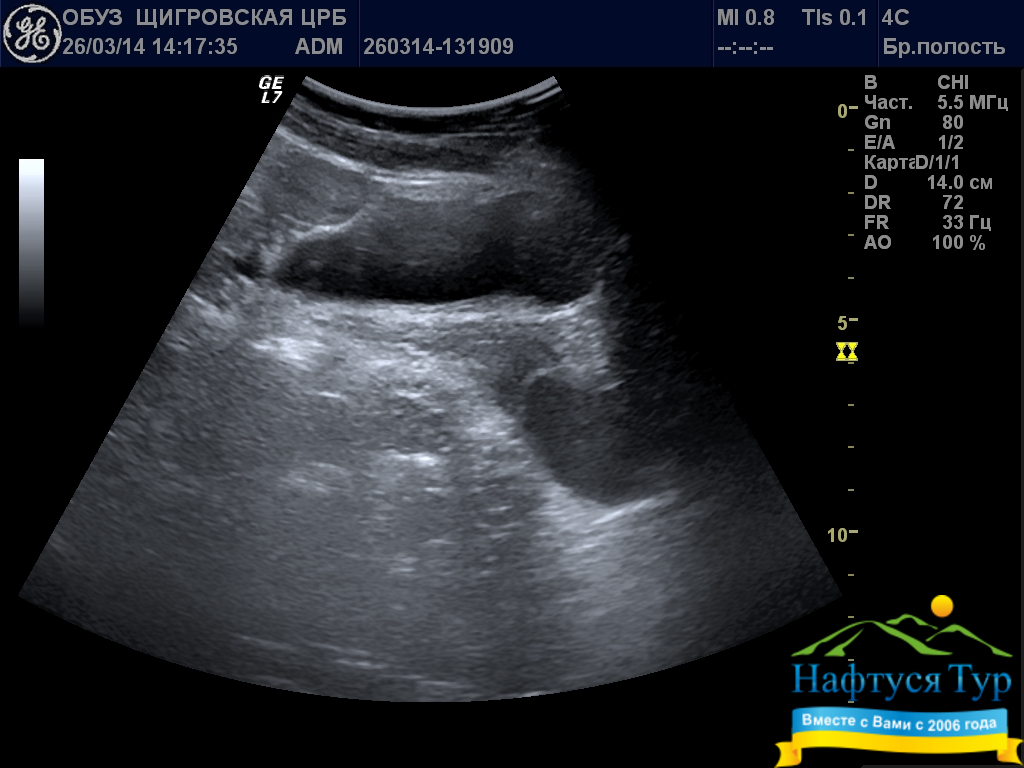

Ультразвуковое исследование (УЗИ, сонография) – неинвазивная диагностическая процедура, основанная на использовании акустических волн ультразвукового (выше порога слышимости для человека) диапазона. Используемая в санаториях техника для проведения УЗИ состоит из генератора и датчика. Генерируемые звуковые волны проникают в глубину тканей человека, при этом различные по типу ткани и инородные образования в разной степени отражают ультразвук. Отраженные волны улавливаются датчиком аппарата, накопленная информация обрабатывается компьютером, что позволяет сформировать изображение исследуемого органа.

Отметим, что многие санатории имеют самые современные модели аппаратов для проведения УЗИ, в частности, позволяющие получать трехмерные и даже 4D (в динамике) изображения. Наиболее часто данный вид исследований назначают при диагностике мочекаменной и желчнокаменной болезни, заболеваниях почек, гипертонии, стенокардии.